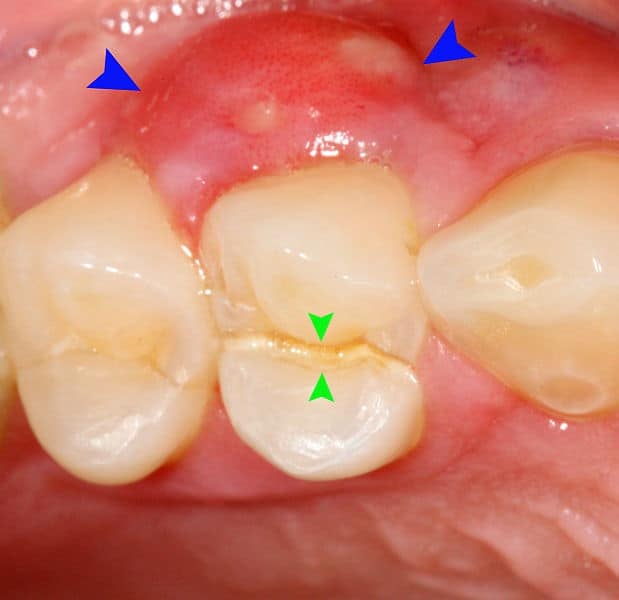

डेंटल एब्सेस दांत और मसूड़ों के अलग-अलग हिस्से में होता है और इसी के आधार पर इसे अलग-अलग कैटेगरी में बांटा जाता है। दांत का फोड़ा के सामान्य प्रकार इस तरह हैः

पेरियापिकल एब्सेस- यह फोड़ा दांत की जड़ों के ऊपरी हिस्से पर होता है।

पेरियोडोन्टल एब्सेस- यह फोड़ा दांत की जड़ों के आगे मसूड़ों में होता है और यह आसपास के ऊतकों और हड्डियों तक भी फैल सकता है।

जिंजिवल एब्सेस- जब फोड़ा मसूड़ों पर होता है तो उसे जिंजिवल एब्सेस कहते हैं।